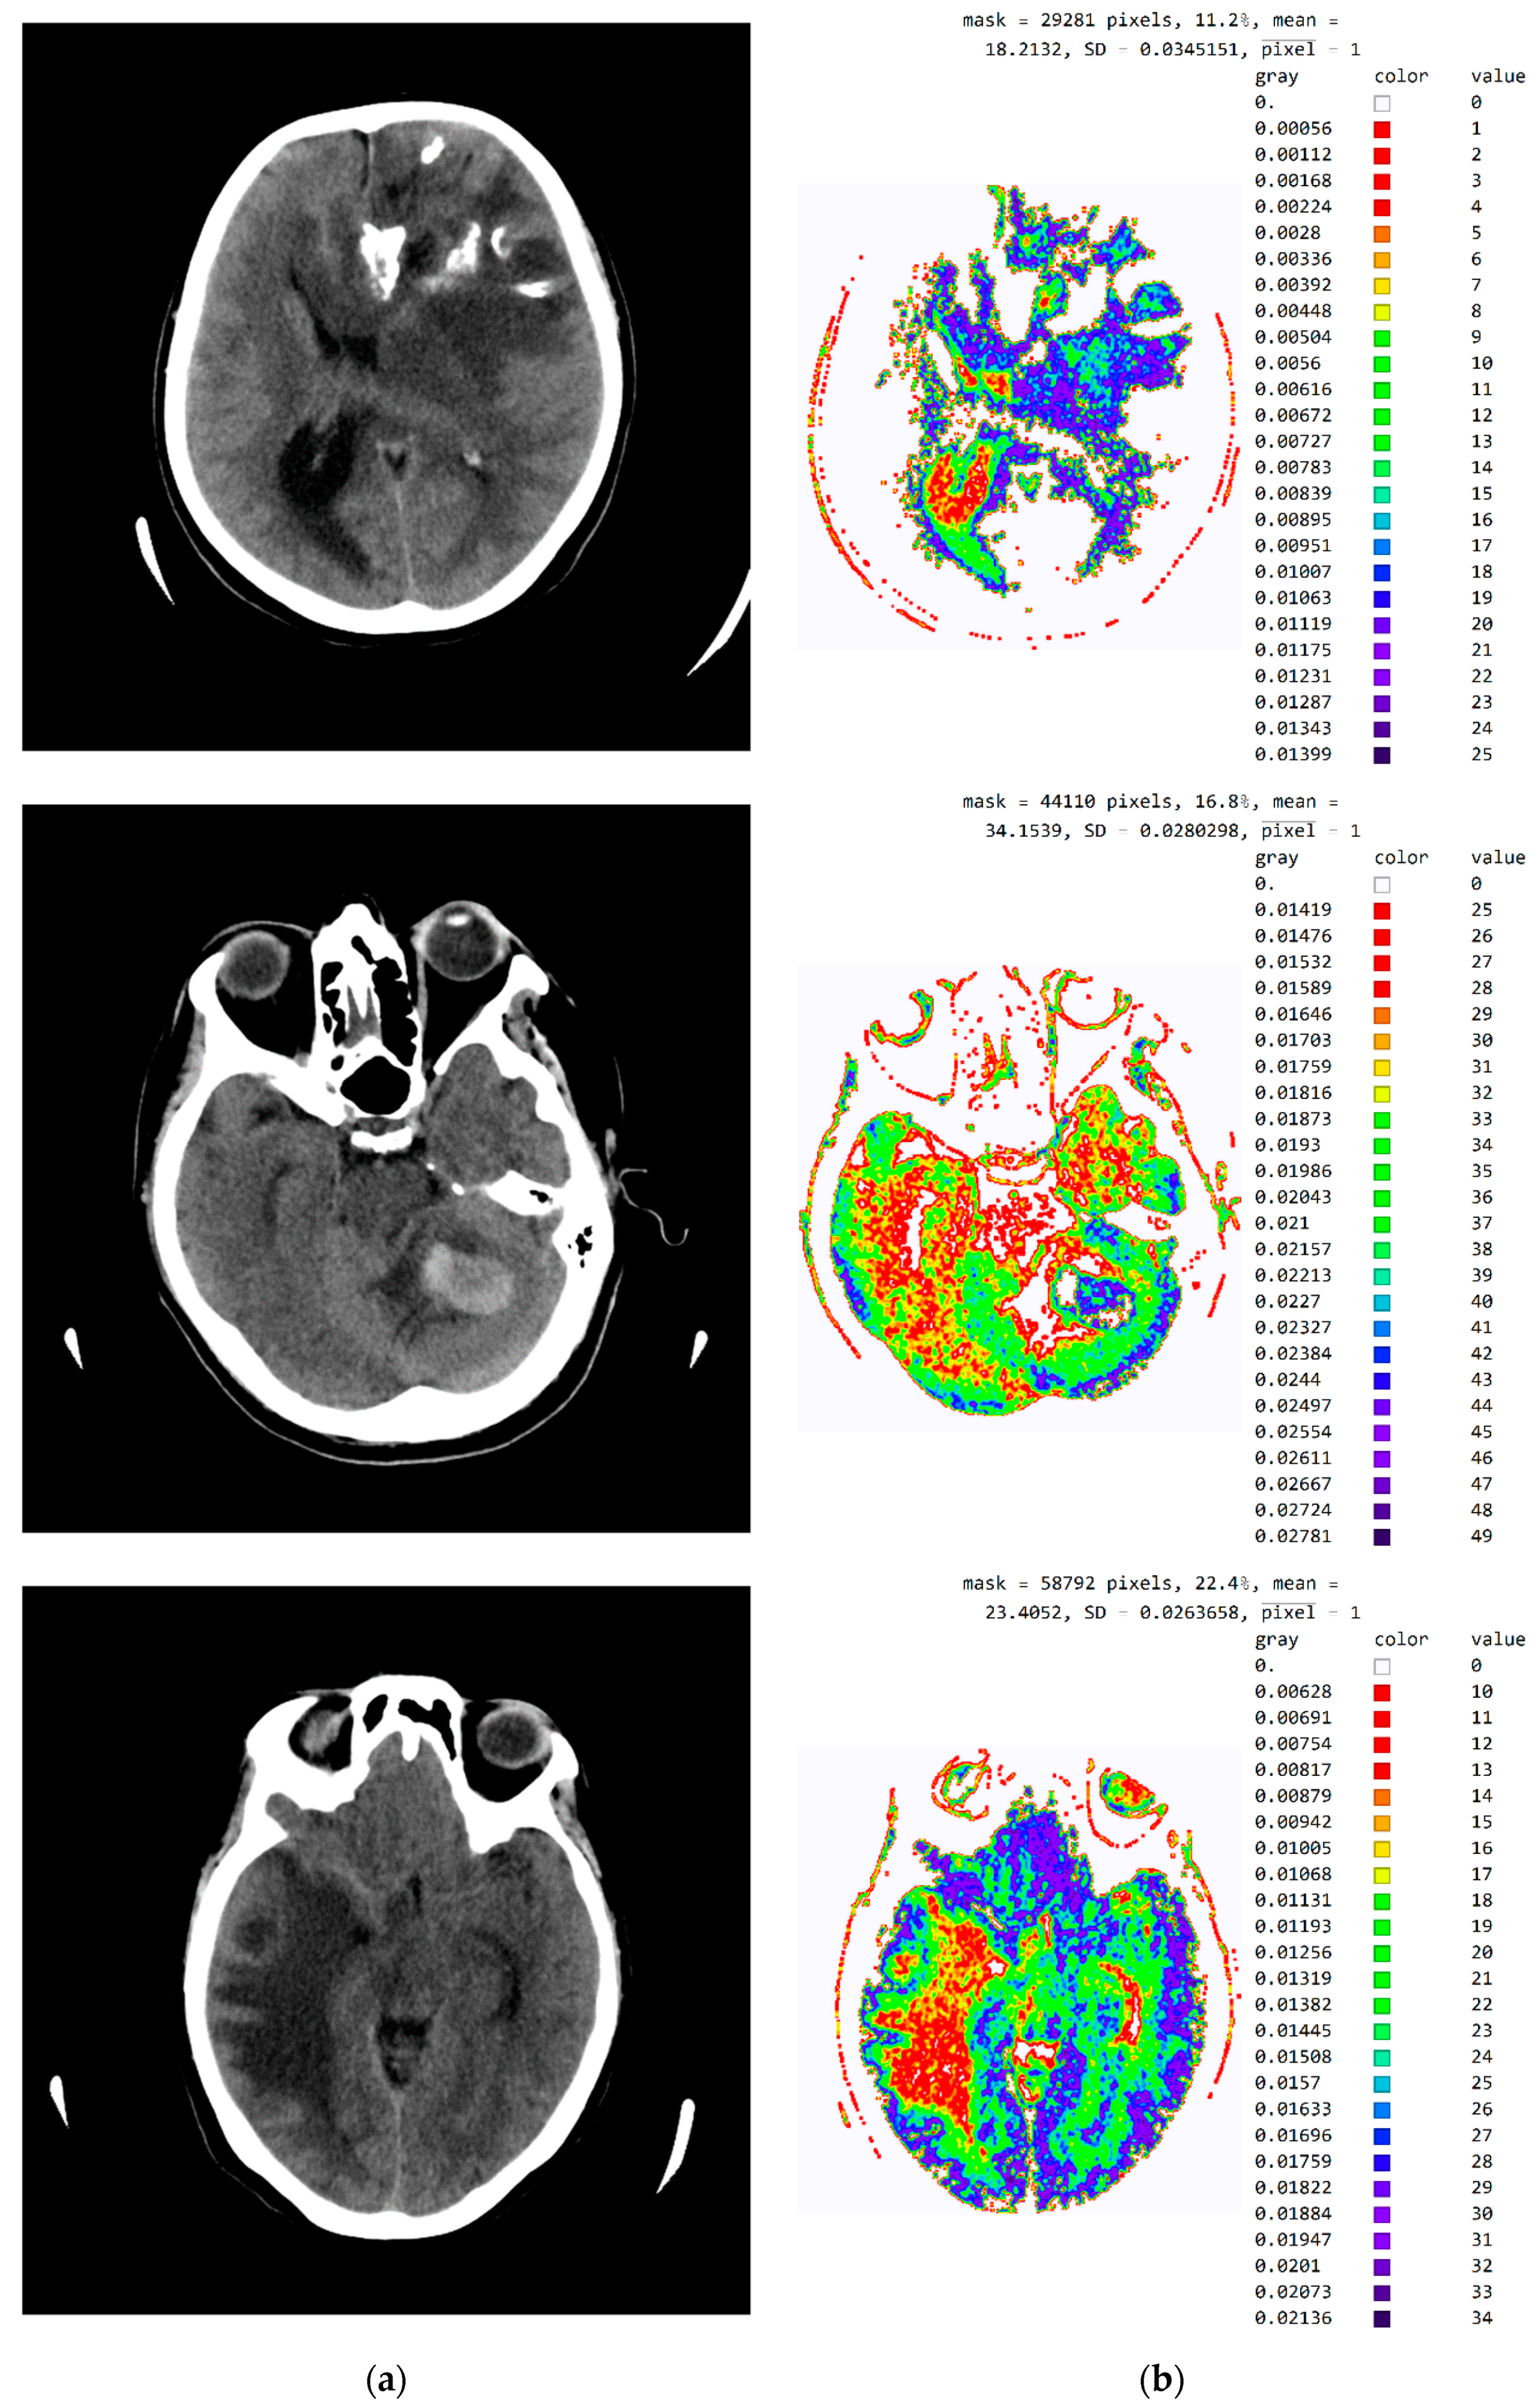

2.2. Smart Visualization Method (SVMI)

3.1. Technological Description